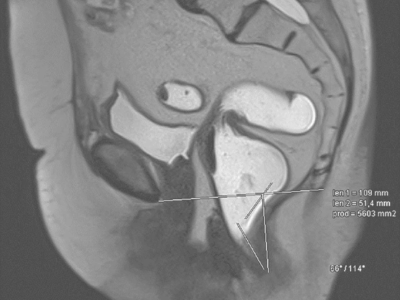

Descensus genitalis und obstruktives Defäkationssyndrom

Häufig geht ein Descensus genitalis auch mit einem obstruktiven Defäkationssyndrom (ODS) oder einer analen Inkontinenz einher. Insbesondere Patientinnen mit kombinierter Symptomatik profitieren von einer interdisziplinären Diagnostik und Therapieplanung. Eine Übersicht über das konservative und operative Vorgehen zeigt dieser Beitrag.

Uterosakralligamente /© T. Fink, Chirurgin und Assistentin bei OP/© Georgiy / stock.adobe.com (Symbolbild mit Fotomodellen), Intrauterinpessar aus Kupfer/© Lalocracio / Getty Images / iStock (Symbolbild mit Fotomodell), Gynäkologische Untersuchung mit Spekulum/© Nomad_Soul / Stock.adobe.com (Symbolbild mit Fotomodellen), Intrauterinpessar/© JPC-PROD / stock.adobe.com (Symbolbild mit Fotomodell), Junge Frau sitzt auf Toilette/© Dragana Gordic / stock.adobe.com (Symbolbild mit Fotomodell), Laparoskopischer Eingriff/© RFBSIP / stock.adobe.com (Symbolbild mit Fotomodellen), Netz und Skalpell/© Beate Panosch / stock.adobe.com, Ärztin zeigt auf Modell eines weiblichen Beckens/© H_Ko / Stock.adobe.com (Symbolbild mit Fotomodell), Frau mit Balsenschwäche/© grinvalds / Getty Images / iStock (Symbolbild mit Fotomodell), Beckenbodentraining/© Mathias Ernert, Atelier Gesundheit, Schwangere macht Gymnastik/© fotostorm / Getty Images / iStock (Symbolbild mit Fotomodell), Transvaginalsonographie in der 11+1SSW/© Springer Medizin, Modell einer Levatoravulsion/© Baeßler K et al. / all rights reserved Springer Medizin Verlag GmbH, Magnetresonanz-Defäkographie des Rektums/© Deniz M, Kornmann M / all rights reserved Springer Medizin Verlag GmbH, Ältere Frau mit Trainerin beim Sport/© jacoblund / Getty Images / iStock (Symbolbild mit Fotomodellen), Laparoskopische Operation/© Iryna / stock.adobe.com (Symbolbild mit Fotomodellen), rotatorischer Descensus urethrae mit einem Meatus urethrae internus/© Anzböck T, Koensgen D: doi.org/10.1007/s00117-023-01215-7 unter CC-BY 4.0, Search Icon, Paar schaut glücklich auf Schwangerschaftstest/© Andrii Zastrozhnov / Stock.adobe.com (Symbolbild mit Fotomodellen), ZFA TALKS - Depression/© (M) seb_ra / Getty Images / iStock (Symbolbild mit Fotomodell) Logo: Springer Medizin Verlag GmbH, Ältere Frau fasst sich an die Brust/© Jelena Stanojkovic / Stock.adobe.com (Symbolbild mit Fotomodell), Person setzt DNS-Probe in Maschine ein/© Vit Kovalcik / stock.adobe.com